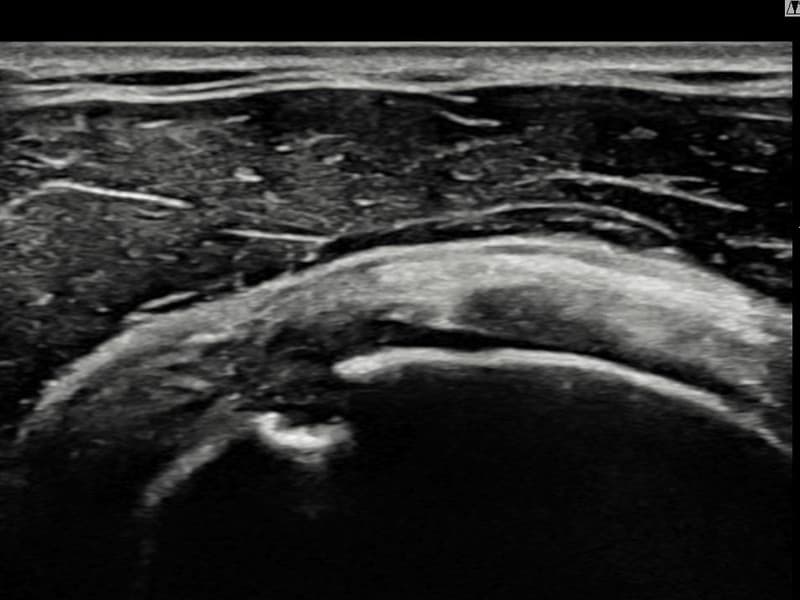

Before

시술 전 초음파 측정 결과 파열 크기는 13mm × 6mm (힘줄 두께의 약 62% 결손)로 확인되었습니다. 시술 전 초음파에서 우측 극상근건 점액낭면측의 광범위한 에코 단절과 힘줄 두께의 현저한 감소가 확인되었습니다. 시술 후 초음파에서 점액낭면측 힘줄 경계가 선명해지고 연속성이 완전히 회복된 것이 관찰되었습니다.

40대 후반 남성 환자분으로, 골프를 즐겨 하시다 스윙 동작 중 어깨에 통증이 생겨 운동을 중단하셨습니다. 이후 통증이 악화되어 팔을 앞으로 뻗거나 위로 올리기도 어려운 상태가 되어 내원하셨습니다. 초음파 검사에서 우측 극상근건 점액낭면측의 광범위한 부분파열이 확인되었으며, 파열 두께와 범위를 고려하여 초음파 유도 하 축소봉합술을 시행하였습니다. 시술은 당일 귀가로 이루어졌으며, 이후 보조기 착용 6주 후 단계적으로 어깨 근력 강화 운동을 진행하였습니다. 시술 9주 후 추적 초음파에서 점액낭면측 힘줄 연속성이 완전히 회복된 것이 확인되어 골프 복귀에 성공하셨습니다.